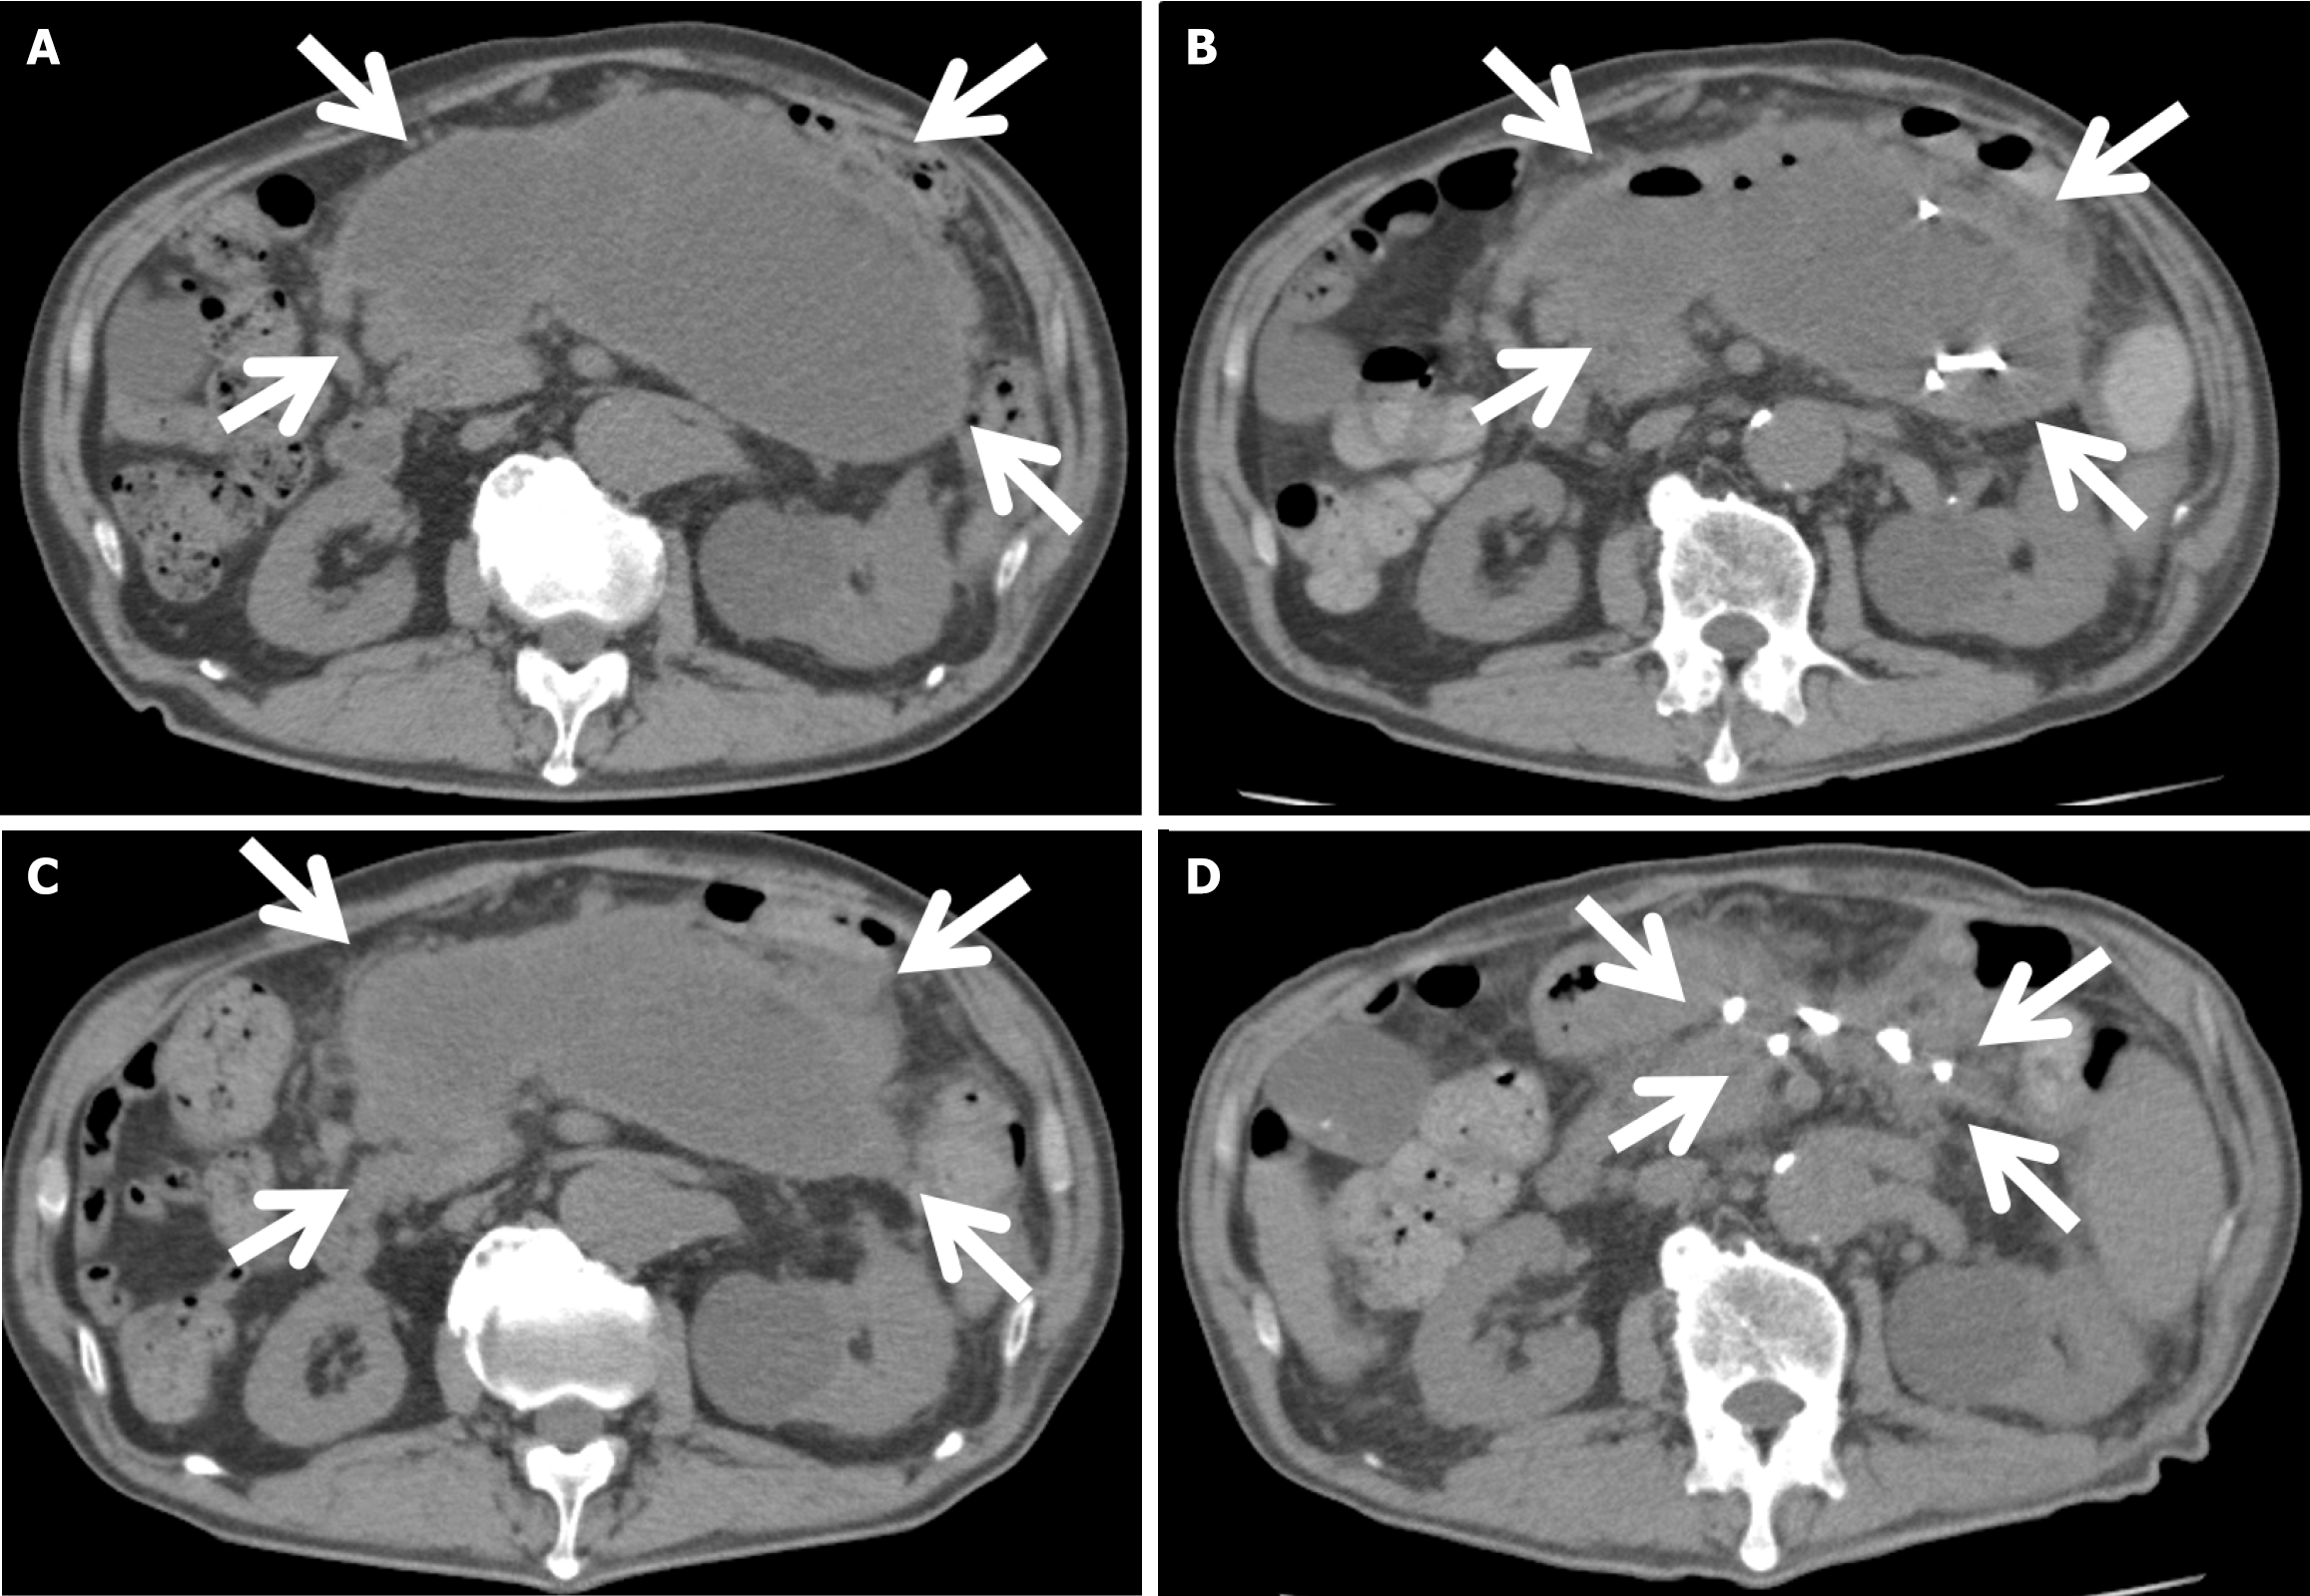

Figure 4 Abdominal computed tomography showing gradual shrinkage of walled-off necrosis.

A: On postoperative day 42 (before the drainage) the diameter of walled-off necrosis (WON) (surrounded by arrows) was 18.5 cm; B: On postoperative day 53 (3 days after the first drainage) the diameter of WON (surrounded by arrows) was 16 cm; C: On postoperative day 63 (13 days after the first drainage, before the second drainage) the diameter of WON (surrounded by arrows) was 18 cm; D: On postoperative day 165 (115 days after the first drainage, 78 days after the second drainage) WON (surrounded by arrows) almost disappeared.